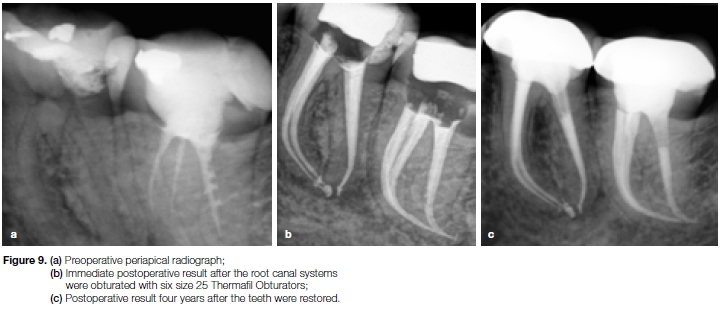

Case report

The patient, a 29 year old female presented with a non-vital mandibular left first molar and a poorly root canal treated second molar (Figure 9a). After removal of the previously placed gutta-percha in the second molar all the root canal systems in both teeth were negotiated to patency.

Glide path preparation was done with PathFiles (Dentsply Sirona) and root canal preparation was done with the X1 and X2 ProTaper NEXT instruments. Obturation of the six root canal systems was effected with size 25 Thermafil Obturators (Dentsply Sirona) (Figure 9b). Figure 9c shows the result at a four year follow up visit.